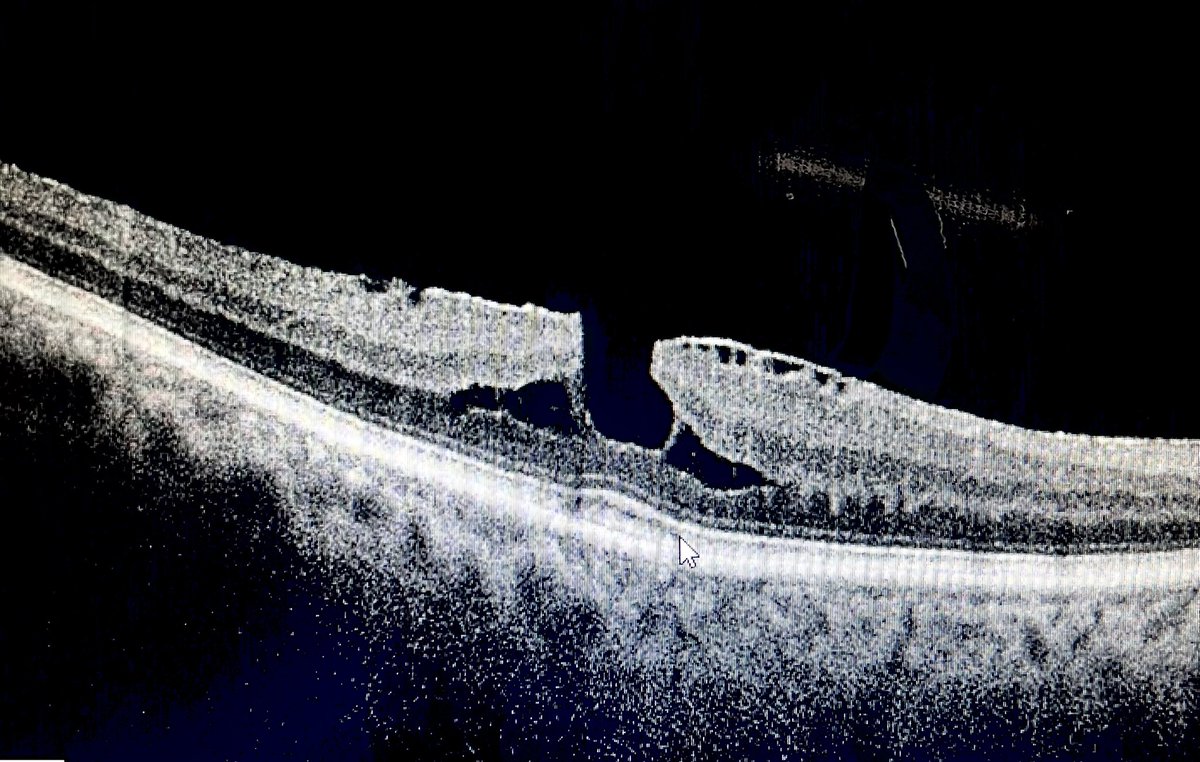

Eye MD | Fixing Eyes in Kashmir ❤️ | Cataract & Retina

🔗 Take the quiz: forms.gle/9DnrCQszG2BzhC… 📢 Clinical Ophthalmology MCQ Self-Assessment now live with answers & explanations across all subspecialties. Designed for postgraduates & residents preparing for IMM/Final fellowship exams. Mazhry-The Poet Ophthalmologist -ماہرِ چشم سخنور Acuity Eye Centre- The care your eyes need! Dr Hammad Nasti